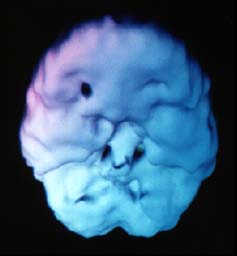

![]() 20 anos de Heroína |

O cérebro do viciado em heroína mostra áreas enormes de diminuição de atividade geral. |